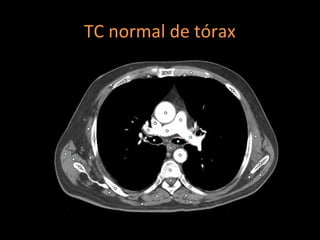

Tomografia computadorizada

Angiotomografia dos vasos pulmonares com TCMD

e reconstruções com filtro de alta resolução;

Mede-se o tronco da pulmonar próximo à sua

bifurcação e lateralmente à aorta ascendente;

Em adultos: até 29 mm;

Sensibilidade: 69-87%;

Especificidade: 89-100%.

TC normal de tórax